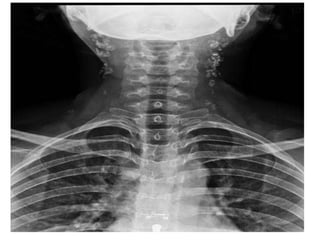

Ultrasound

• Ultrasound is an excellent first-line investigation as it

assess cervical lymphadenopathy and also enables

guided fine needle aspiration cytology.

• The combination of grey-scale imaging and FNAC as a

sensitivity of 92% and specificity 97% in distinguishing

benign from malignant nodal disease.

• Differentiating features from neck metastasis include:

– Nodal matting

– Surrounding soft tissue oedema (less marked than one

would expect given the size of the collections)

– Homogeneity

– Intranodal cystic necrosis and

– Posterior enhancement.

• Doppler examination is particularly useful in

helping distinguish tuberculous infection from

necrotic metastatic disease.

• Reactive nodes (including those in tuberculous

lymphadenitis) demonstrate prominent

vascularity, but mostly confined to the hilum,

whereas malignant nodes demonstrate more

peripheral/capsular vascularity.